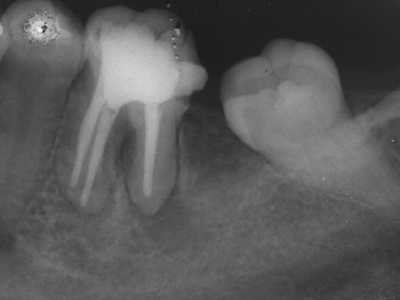

RCT is performed for apical periodontitis to remove infected tissue from the root canal, facilitate periapical tissue repair, and prevent further infection. The goal is a non-surgical, tooth-saving therapy to eliminate bacteria and seal the root canal system. While success rates for primary RCT are high (68-85%), healing can take months to years, and a successful coronal restoration is critical for long-term tooth survival.

Clinical & Radiographic Monitoring :

Healing is assessed by clinical signs and radiographic changes in the periapical tissue over time, with complete healing sometimes taking several years